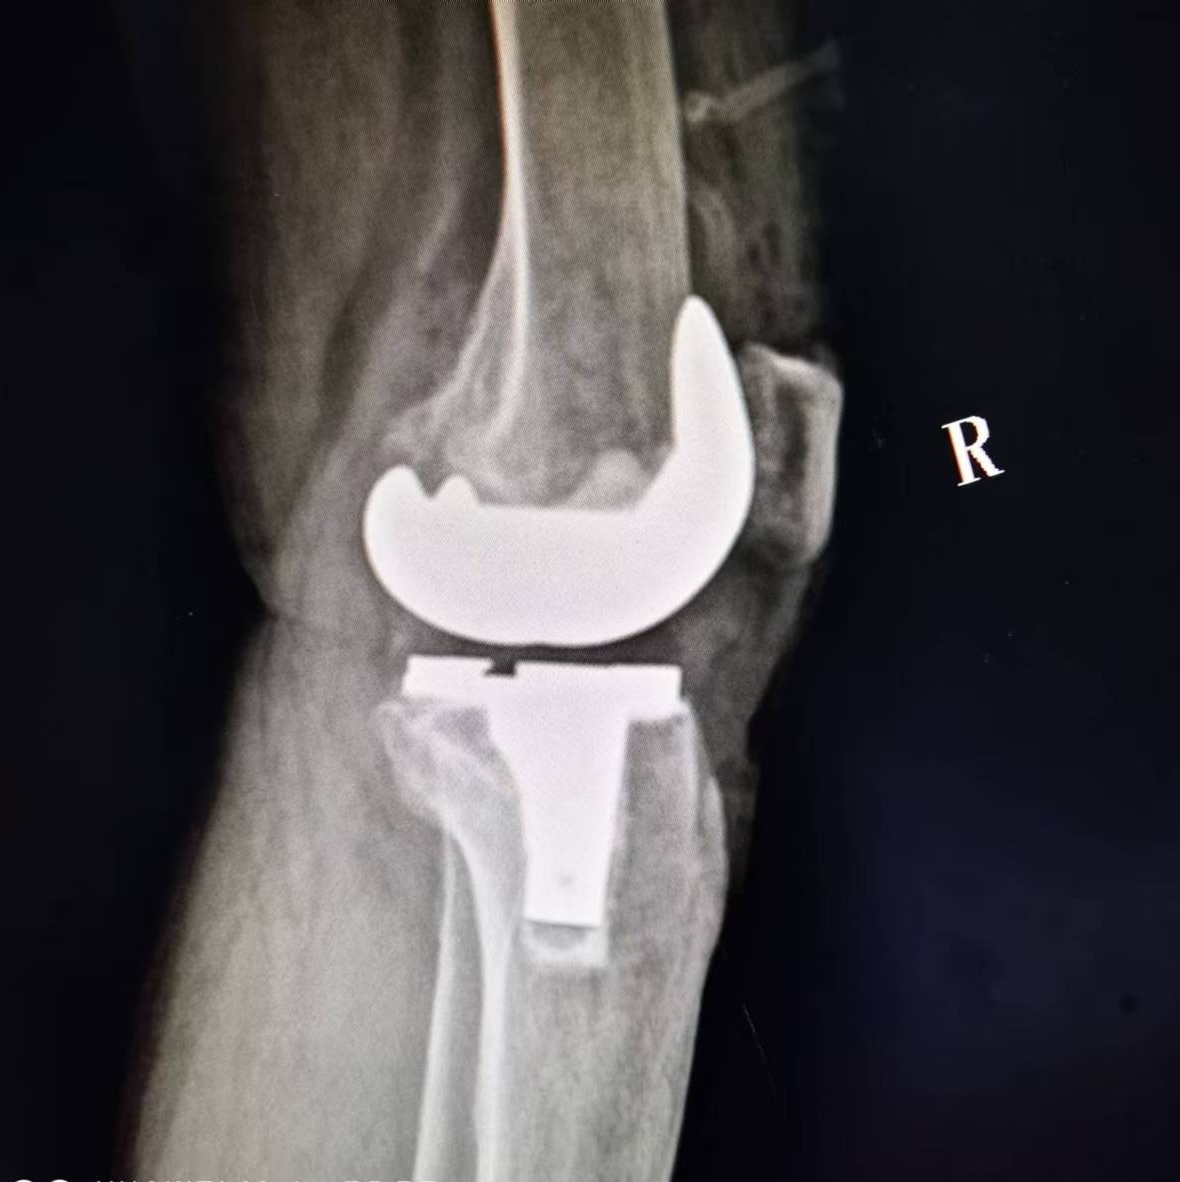

术 后